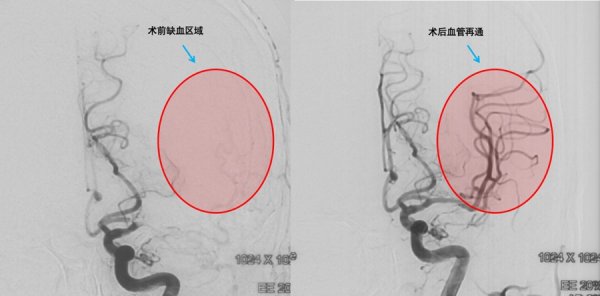

近日,90岁高龄的张爷爷从上海四一一医院顺利康复出院。这场与死神的赛跑中,医院多学科团队凭借精湛医术和高效协作,成功将老人从死亡线上拉回,赢得家属连连称赞。 3....